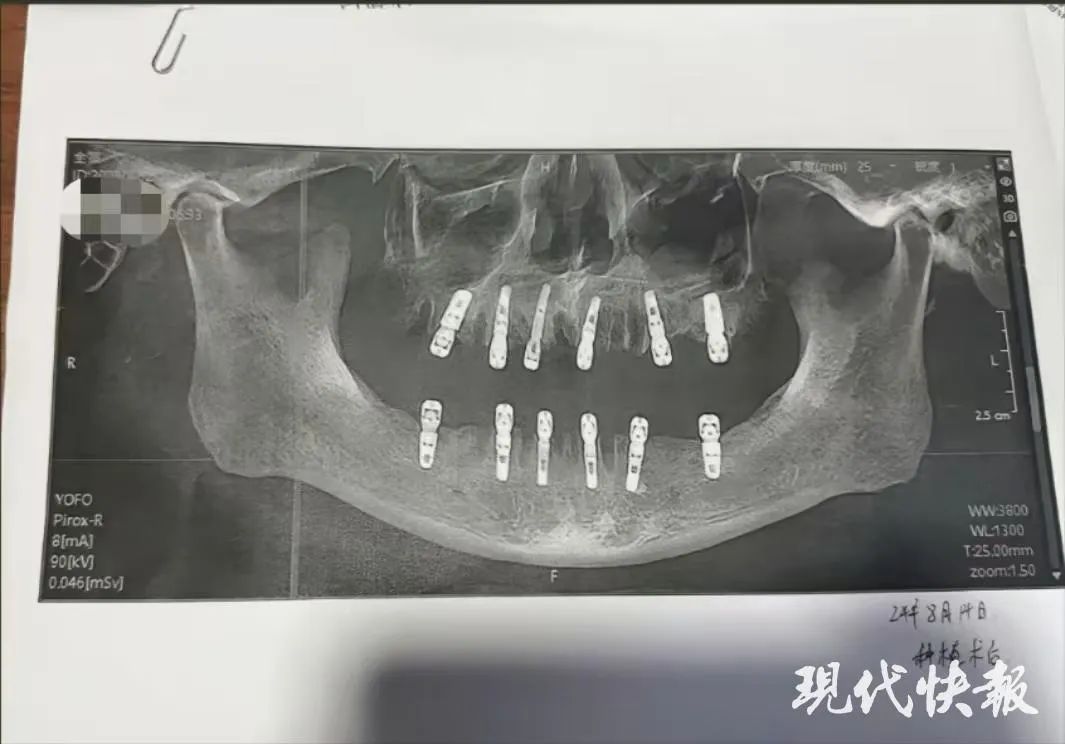

舒女士介绍,父亲黄某8月14日在德维口腔医院接受牙科手术。据黄某签署的种植手术同意书显示,本次治疗拔牙23颗、种植牙齿12颗,并且均为即刻修复,即“当天拔、当天种”,负责治疗的医师为袁某。

不过,在黄某的种植手术同意书中显示,他的多颗臼齿在拔除当天就进行了种植,与工作人员介绍的并不相符。